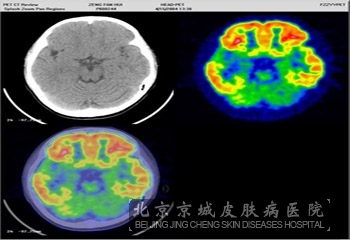

北京京城皮肤医院介绍说:结节硬化症的脑部病变主要表现为在大脑皮质有很多硬实的结节吗,这些结节性的损害主要出现在大脑白质以及灰质中,而且白质内有异位*团,脑室壁内亦有小结节皮质结节的数不一,一般出现在额叶,而且比较严重;还会出现在丘脑、基底节小脑脑干等部位。